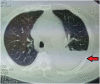

Trichoderma longibrachiatum is a fungus belonging to the genus Trichoderma. Trichoderma longibrachiatum is not thought as a pathogenic for healthy individuals. However, it has the ability to produce toxic peptides and extracellular proteases and has been described to cause invasive infections in immunocompromised hosts. Trichoderma longibrachiatum has been reported as the causative microorganism of lung infections, skin infections, sinus infections, otitis, stomatitis endocarditis, pericarditis, gastrointestinal infections, mediastinitis and peritonitis. We report the first case of pneumonia with parapneumonic effusion in an old woman with diabetes mellitus due to Trichoderma longibrachiatum.